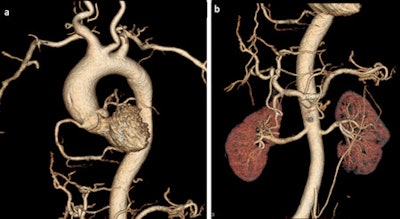

The development of postmortem CT angiography (PMCTA) represents a significant step forward to minimally invasive autopsies, but considerable work still has to be done before it can replace the conventional autopsy, Swiss researchers have found.

To help propel PMCTA from the research lab to routine practice, techniques need to be further investigated and standardized, and their artifacts, strengths, and pitfalls must be known and guidelines for the interpretation of the radiological data should be available. Only then can the techniques be used in sensitive medicolegal cases and can they be introduced into the workflow of a daily routine, noted Dr. Silke Grabherr, PhD, and colleagues, from the University Center of Legal Medicine Lausanne-Geneva, University Hospital of Lausanne in Switzerland.

"Beside the validation of the existing techniques, there are also further things to develop: Protocols for the investigation of superior and inferior members should be established, perfusion protocols for infants are needed, and methods for selective angiography other than the coronary arteries would be of interest. All these missing points underline that the research of PMCTA is still in the beginning," stated Grabherr et al.

The research group in Lausanne is doing multiple studies involving the technique of multiphase PMCTA (MPMCTA). Also, different research projects of the TWGPAM members are ongoing, such as studies about vascular lesions due to road traffic accidents, medicolegal investigations of medical errors using MPMCTA, and the use of MPMCTA for investigating cases of sharp trauma, as well as technical studies to investigate new selective cannulation approaches, etc.